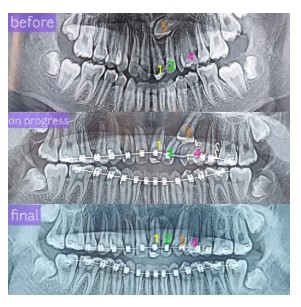

KASUS IMPAKSI GIGI TARING ATAS (GIGI TARING MASIH TERTANAM DALAM TULANG)

Pasien laki-laki 14 thn dengan keluhan gigi-giginya kurang rapi dan terdapat gigi taring atas kiri yang ukurannya kecil. Pasien memperkirakan gigi tersebut adalah gigi susu karena merasa gigi tersebut tidak pernah tanggal atau goyang.

Dari pemeriksaan klinis, terlihat di area yang harusnya terdapat gigi taring permanen ada gigi yang ukurannya lebih kecil dari gigi-gigi yang lain.

Dari pemeriksaan panoramik, terlihat gigi yang kecil tersebut adalah gigi susu yaitu memiliki ukuran kecil dgn akar yg pendek. Terlihat juga gigi taring permanen yg impaksi dengan posisi yg cukup sulit yaitu di area dekat akar antara gigi insisif satu dan insisif dua. Gigi impaksi adalah gigi yg tidak dapat tumbuh, baik sebagian atau seluruhnya sehingga tertanam di dalam tulang.

Pada kasus ini pasien dirawat menggunakan bracket Self Ligating, dilakukan tindakan windowing (tindakan pembedahan yang dilakukan untuk membuka sedikit area pada gigi yg impaksi agar dapat di pasangkan attachment). Pada kasus ini hanya dilakukan pencabutan pada gigi taring susu yg masih ada.

Setelah sekitar 2 tahun perawatan, gigi taring impaksi sudah berada di posisi yg benar. Saat ini perawatan masih dilanjutkan untuk mendapatkan oklusi yg lebih baik.